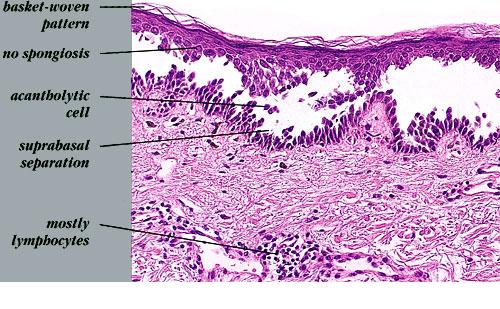

The earliest recognized change may be either eosinophilic spongiosis rarely or, more commonly, “spongiosis” in the lower epidermis . This spongiosis may actually represent the earliest manifestation of acantholysis rather than true spongiosis as defined earlier. Acantholysis leads first to the formation of clefts and then to blisters in a predominantly suprabasallocation . The intraepithelial acantholysis may extend into adnexal structures or occasionally be higher in the stratum spinosum. The basal keratinocytes, although separated from one another through the loss of attachment, remain firmly attached to the dermis like a “row of tombstones.” Within the blister cavity, the acantholytic keratinocytes, singularly or in clusters, have rounded condensed cytoplasm about an enlarged nucleus with peripherally palisaded chromatin and enlarged nucleoli. In some patients, there are varying quantities of antidesmoglein 1 and antidesmoglein 3 antibodies, leading to variable planes of acantholysis. There is little inflammation in the early phase of blister formation. If present, it is usually a sparse, lymphocytic perivascular infiltrate accompanied by dermal edema. However, if eosinophilic spongiosis is apparent, numerous eosinophils may infiltrate the dermis. The phenomenon of eosinophilic spongiosis occurs occasionally in other blistering diseases, particularly in their early phases, including acute contact dermatitis, pemphigus foliaceus, bullous pemphigoid, herpes gestation is, drug eruptions, spongiotic arthropod bite reactions, and transient acantholytic dermatosis. Several important changes ensue as the lesions age. First, a mixed inflammatory cell reaction consisting of neutrophils, lymphocytes, macrophages, and eosinophils may develop. Because of the instability of the blister roof, erosion and ulceration may occur. Older blisters may also have several layers of keratinocytes at the blister base because of keratinocyte migration and proliferation. Last, there may be considerable downward growth of epidermal strands, giving rise to so-called villi (Fig. 9-9D). The evaluation of patients with only oral lesions is difficult, because intact blisters are rarely encountered due to the trauma of mastication, and biopsies may show only erosion and ulceration. Indeed, it is best to sample the edge of a denuded area with intact mucosa in an attempt to demonstrate the typical pathologic changes. Clinicians frequently cannot distinguish between an ulcer and the intact mucosa, as both are often white and shaggy. In patients with only oral lesions, biopsies of intact oral mucosa for DIF testing are more sensitive than biopsies of lesions for routine light microscopic evaluation. Therefore, biopsy from the normal maxillary and upper buccal mucosa is necessary when there is extensive ulceration. Cytologic examination using a Tzanck preparation is useful for the rapid demonstration of acantholytic epidermal keratinocytes in the blisters of pemphigus vulgaris. For this

Differential DiagnosisIn early blisters that are free of secondary changes, such as the degeneration or regeneration of epidermal cells, the histopathology of pemphigus vulgaris is characteristic. Important differential diagnoses include Hailey-Hailey disease and transient acantholytic dermatosis. Hailey-Hailey disease has full­thickness (“dilapidated brick wall”) acantholysis, epidermal hyperplasia, and an impetiginized scale crust. The acantholysis does not extend down follicles as it does in pemphigus. Transient acantholytic dermatosis may exhibit small foci of intraepidermal acantholysis, but these are only a few rete wide in contrast to the uniform widespread acantholysis observed in biopsies of pemphigus vulgaris. Disorders such as Darier’s disease that are characterized by acantholytic dyskeratosis are readily separated from pemphigus vulgaris by the presence of abnormal granular keratinocytes and parakeratotic cells, so-called corps ronds and corps grains. Although light microscopic examination of pemphigus lesions is important, positive DIF is the gold standard in diagnosis at this time and must be pursued in all cases in which pemphigus vulgaris is considered.